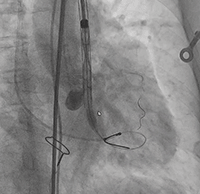

行左冠保护,预置左冠球囊

输送器系统跨瓣后,出现血压异常降低,血压下降至55/30mmHg,给予升压药物无效。

● 考虑冠脉保护球囊置入较深可能影响冠脉灌注?

冠脉造影评估灌注后撤出球囊,血压未回升,给予升压药物仍无法回复血压。